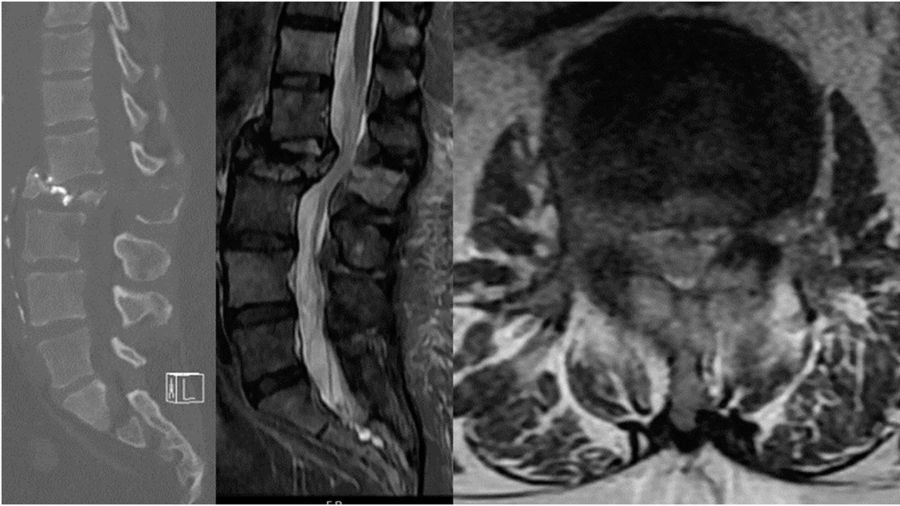

Case 1: A 46-year-old man presents with 3 months of weight loss, back pain, and cough. He is a non-smoker.

Chest imaging reveals a lung nodule consistent with NSCLC (adenocarcinoma) and molecular analysis reveals an EGFR mutation. There is a single metastatic lesion at L2 causing a pathologic fracture with greater than 50% loss of height and retropulsion. He is ambulatory and has pain-limited weakness 4/5 on the hip flexor. He has good performance status (ECOG 1) and his Spine Instability Neoplastic Score is 17. Given the recent diagnosis of NSCLC and the favorable EGFR mutation, patient is started on osimertinib and offered separation surgery plus stabilization.